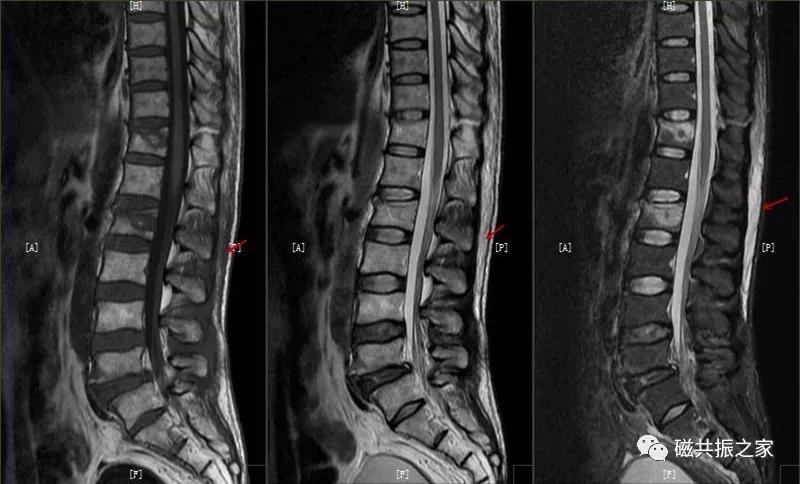

12.休门病/许莫尔结节/椎体边缘骨

休门病(Scheuermann,sdisease),主要由椎板骨软骨炎引起骨生长障碍,常见于青少年胸腰椎脊柱病变。

主要表现:椎体发育异常,椎体楔形改变,高度变低,前后径正常,常形成脊柱后凸畸形。

在矢状面上T1WI和T2WI显示各椎体楔形变,椎体高度减小,椎间隙变窄。椎体后1/3区呈多发性小骨质凹陷的Schmorl结节改变,髓核组织突入其中,边缘清楚,常呈上下对称分布,青少年病变周围可见长T1长T2信号,提示骨小梁水肿。

许莫尔结节(Schmorl,snodes),是休门病的一个病例征象。1930年Schmorl对照检查8000例尸检和X线发现椎体生长板发育不完善,或后天外伤致椎间盘突入椎体骨松质内,形成椎体压迹,是休门病的主要征象之一。除休门病外,其他的原因引起的生长板破坏,也可能产生Schmorl结节样改变。

矢状面显示椎体上或下椎间盘面异常信号,常呈长T,长T2信号,见髓核信号突入椎体内,常伴椎间隙变窄,常见于L3~S1椎体。

椎体边缘骨,类似于Schmorl改变,一类是椎体生长板和椎体二次骨化中心软骨发育异常,致其不能完全愈合,造成的椎间盘疝入其间,形成边缘体的椎体边缘骨。

另一类是椎体后缘骨内软骨结节,椎间盘疝入骨内,形成椎体后缘的Schmorl结节样改变,椎体终板及髓核等突入其中,椎体骨质增生,常见于L4、L5椎体下缘。